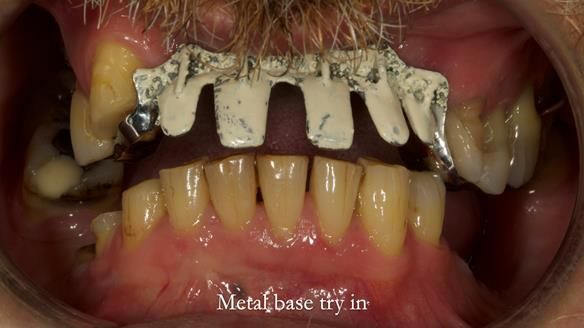

Keith’s case was one of the most challenging and rewarding cases I’ve treated this year. This 64 year old man presented with ill-fitting acrylic partial dentures that lacked stability, retention, and aesthetics. They constantly broke. He had lost the upper front teeth in a road traffic accident in his early 20s. The unopposed teeth had erupted, taking up space. After careful planning, we made a durable, metal-based upper partial denture/splint to address his dental concerns. He loved the outcome.

1. Denture design: A custom cobalt-chromium framework was Scandinavian-designed to maximise stability, protect the remaining teeth, and allow for future additions if needed.

Keith’s denture incorporated a Duracetal shell clasp on upper right first premolar (Myerson), which are designed to be virtually visible, providing a more aesthetic solution while enhancing patient comfort. The Scandinavian-inspired approach, based in modern removable prosthodontic techniques, ensured the denture was not only durable but also visually pleasing. Additionally, the design was carefully planned to allow for future modifications, ensuring that if Keith loses additional teeth, the denture can be adapted rather than replaced entirely.

I also used the Dahl concept to re-establish the occlusion upon fitting the RPD, which helped to intrude the lower left canine without needing to grind it too much.